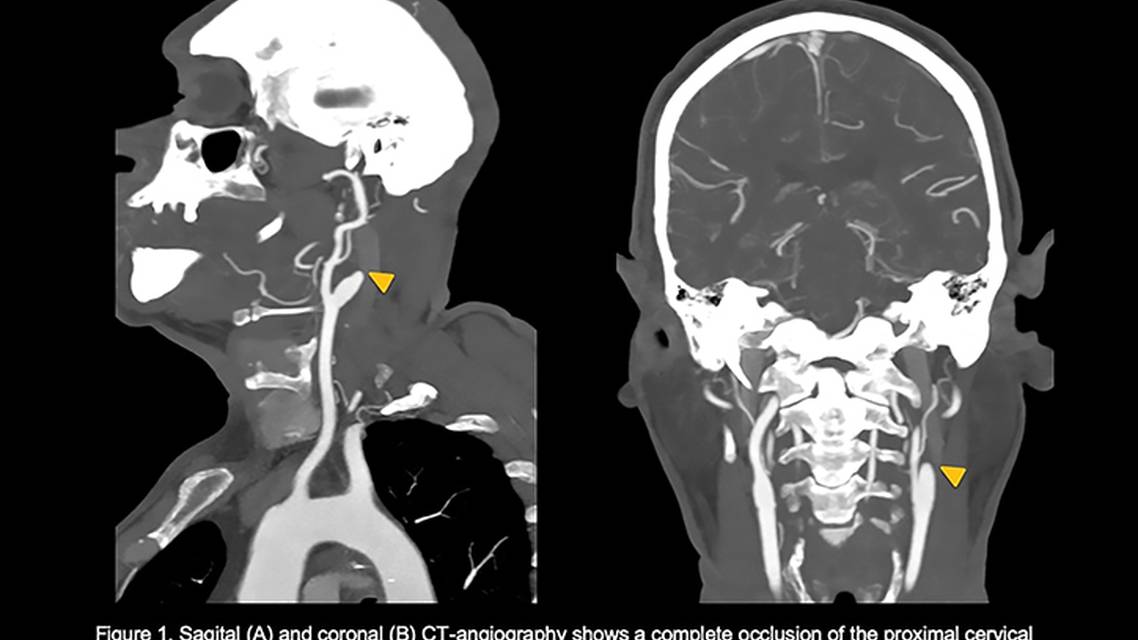

Vital signs were normal on admission, and apart from mild hyperglycemia (146 mg/dL), no other relevant abnormalities were noted on blood test results, including C-reactive protein and erythrocyte sedimentation rate. SARS-CoV-2 antigen test and polymerase chain reaction testing were negative. Initial CT angiography of the head showed a mildly hypodense area in the left white matter with watershed distribution and a large vessel occlusion in the first segment of the left internal carotid artery, with predominant visualization of the right anterior circulation, suggesting detour of blood flow away from the infarct site (Figure 1). The contralateral carotid system showed only mild (30%) calcified plaque in the distal right common carotid artery.